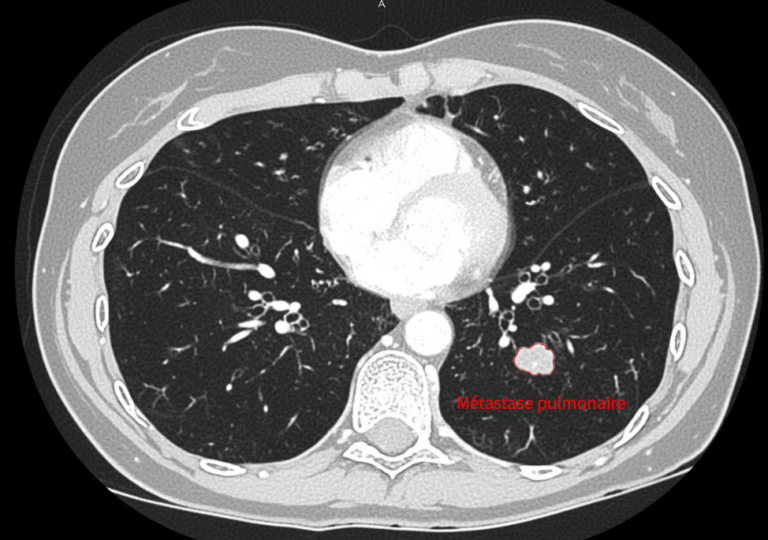

Suivie pour un cancer colorectal métastatique, elle présente une nouvelle récidive avec :

• une métastase pulmonaire de 2,5 cm, située près de structures centrales,

Traitement pulmonaire par cryoablation

La lésion pulmonaire est traitée par cryothérapie, permettant une destruction efficace tout en évitant une chirurgie lourde (lobectomie).

Un pneumothorax, complication attendue, est pris en charge simplement avec un drain temporaire.

Images du traitement des organes (poumon et foie) avant, pendant et après le traitement.